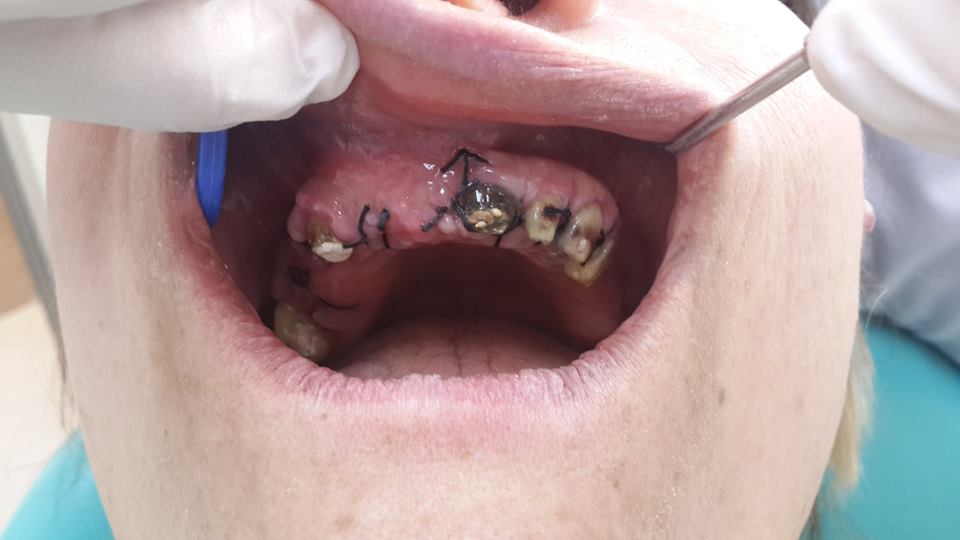

An example of complete rehabilitation of the oral cavity. Treatment included the removal of the old prosthesis, treatment of paradontitis, removal of a large cyst, implantation, clasp prosthesis.